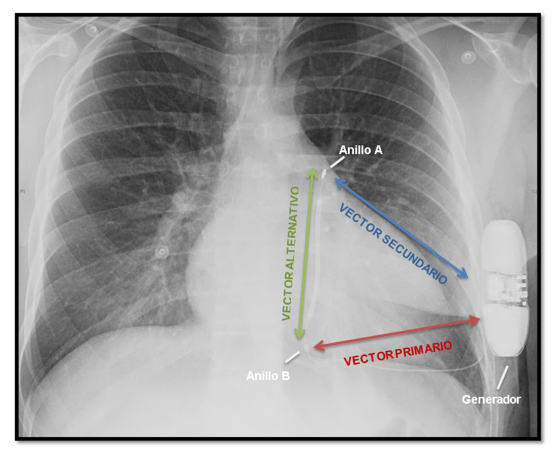

Ricardo Speranza1, de Zuloaga Claudio1, Gustavo Costa1, Romina Dal Fabbro1,2, Patricia Kazelian2, Marcelo Robi1, Daniel Deluso1, Mauro Baliño1, Andrés Bielecky1, Camila Olivera1, Osvaldo Pérez Mayo1, Dr. Claudio Ruiz3. 1Servicio de Electrofisiología y Marcapasos....